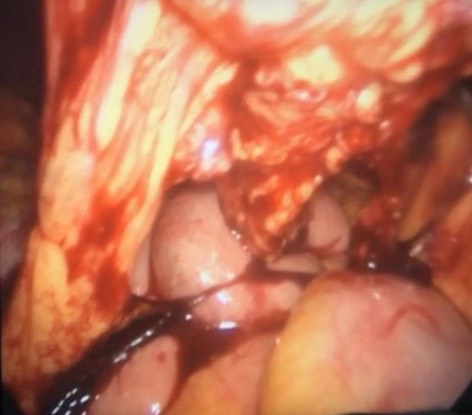

Laparoscopic approach for huge benign ovarian cyst in woman with history of previous 5 laparotomies (including 4 cesarean section)

An adnexal mass (mass of the ovary, fallopian tube, or surrounding connective tissues) is a common gynecologic problem. In the United States, it is estimated that there is a 5 to 10% lifetime risk for women undergoing surgery for a suspected ovarian neoplasm. Adnexal masses may be found in females of all ages, from fetuses to older adults, and there are a wide variety of types of masses. Today, the surgical treatment has become more conservative and less invasive; hence, a laparoscopic approach in the presence of benign cysts has become a golden standard. In the past, patients with previous abdominal surgery were discouraged from undergoing laparoscopic surgery because of its increased risk of bowel injury caused by needle and trocar insertion. Complications occur two times more frequently in patients with previous laparotomy in a study of long series. The potential risk for injury of organs adherent to the abdominal wall during veress needle or trocar insertion as well as the necessity for adhesiolysis and its attendant complications are the two major specific problems constraining surgeons from performing laparoscopic cystectomy/ oophorectomy for patients with previous abdominal surgery. Herein, we report a case of a 32-year-old woman P4 + 2 with history of previous four cesarean section and a following laparotomy for interval sterilization presented to our clinic with abdominal mass, discovered by ultrasound scan, managed by a laparoscopic approach.